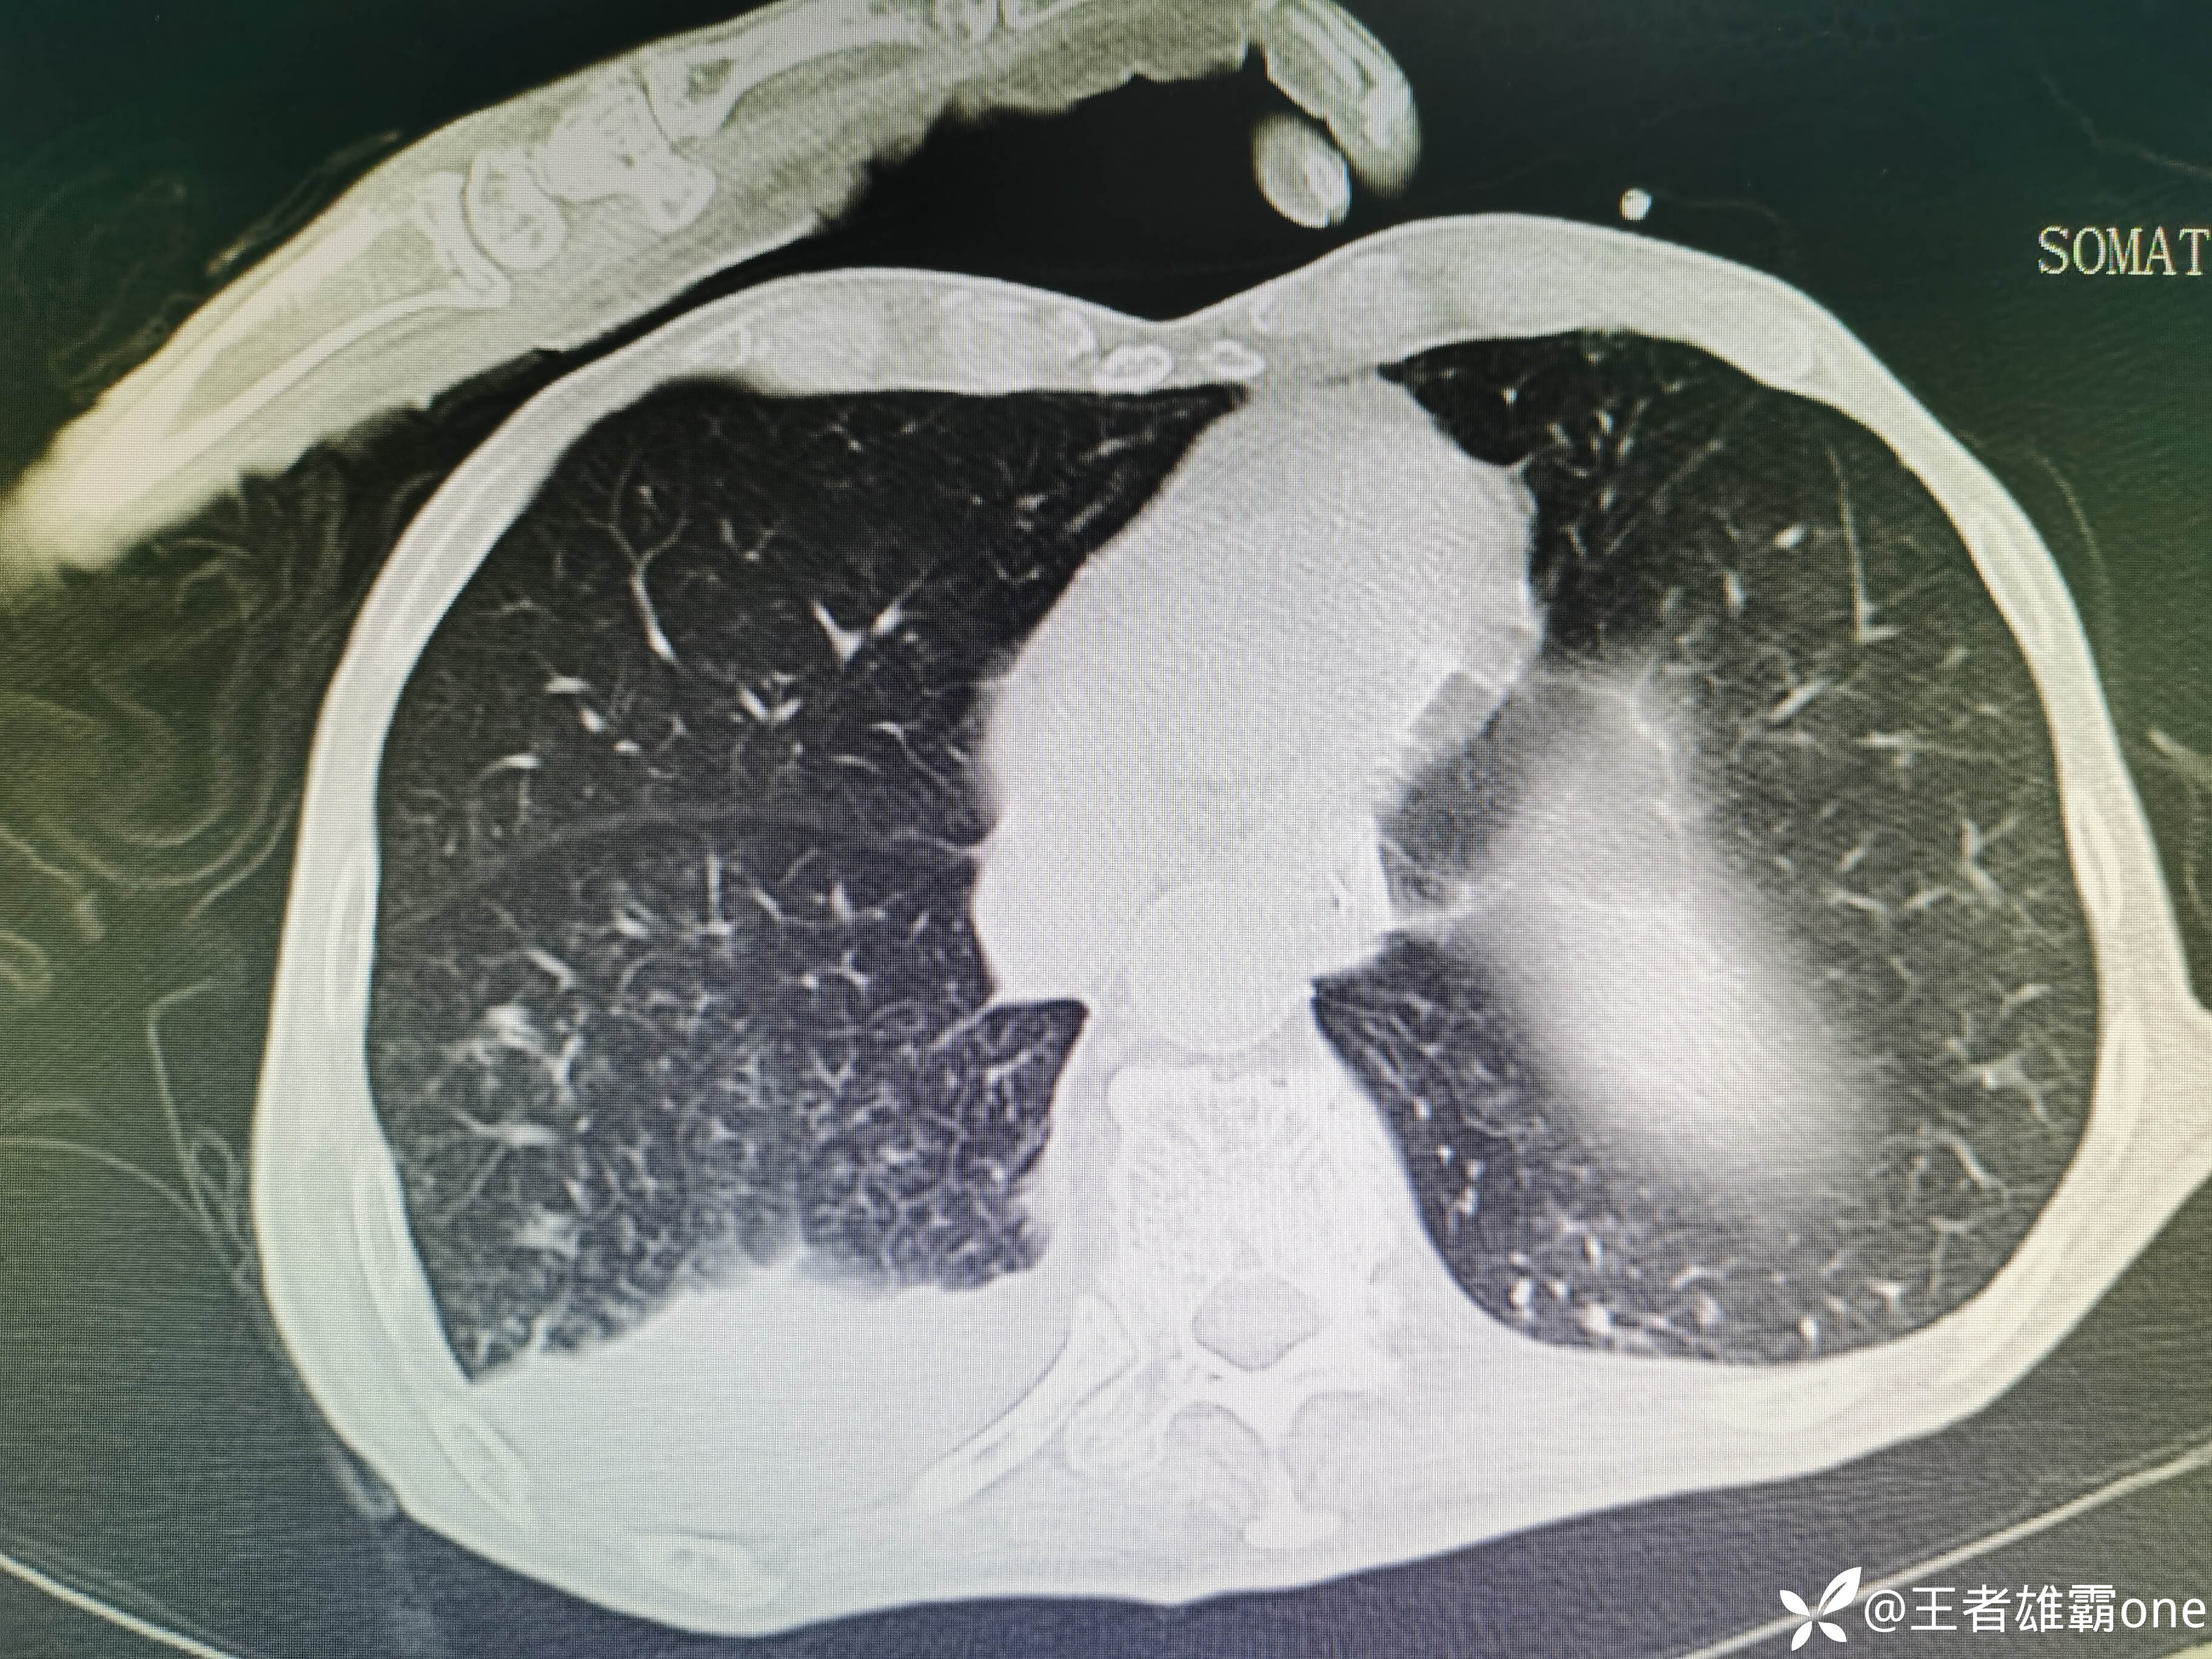

入院时胸部CT:

具体图片: